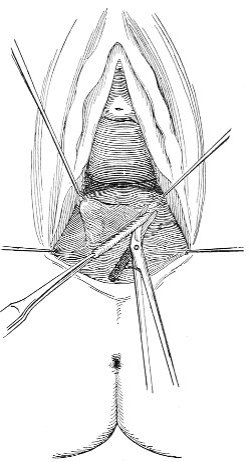

The secondary operation is performed at any time after cicatrization has occurred—often many years after the receipt of the injury. This operation is at present one of the commonest in gynecology, because the injury is not detected, is neglected, or is improperly repaired after labor. In the secondary operation an anesthetic is necessary. The mucous membrane must be removed or denuded on the posterior wall and about the mouth of the vagina, in order that the lacerated structures may be brought again in apposition. The denudation is best made by means of scissors curved on the flat (Figs. 24 and 25).

The strip of mucous membrane to be removed is picked up with a tenaculum (Fig. 26) or with tissue forceps 65 (Fig. 27); the scissors are placed with the blades parallel to the surface to be denuded, and the strip is cut away evenly, in one piece if possible. A similar contiguous strip is removed, and so on until the necessary surface is bare. Sponges in holders (Fig. 28) or continuous irrigation may be used to remove blood.

The special forms of operation will be discussed in the consideration of the varieties of perineal injury.

Slight Median laceration of the Perineum.—In this injury the tear takes place through the fourchette. Posteriorly it may extend as far as the sphincter ani muscle. Upward it may extend for an inch up the posterior vaginal wall. The appearance of this tear is shown in Fig. 33. It will be noted that, as this tear takes place in the median line, none of the muscles that support the perineum are involved, nor are the planes of fascia injured. The perineum is slightly split, and the insertions and origins of the muscles and the fascia are slightly separated. The supporting structures of the perineum and the pelvic floor are, however, uninjured.

Fig. 33.—Recent slight median laceration of the perineum: sutures introduced.

If this tear is detected after labor, it should be closed by the immediate operation. A slight tear involving chiefly the cutaneous aspect of the perineum should be closed by three or four sutures introduced from the outside, as in Fig. 33. The needle should be introduced about a quarter of an inch from the edge of the wound. It should not be passed parallel with the plane of the lacerated surface, but should be swept outward and then inward toward the 68 angle at the bottom of the tear (Fig. 34). It may either emerge at the angle and be re-introduced, or it may be passed directly through to the skin-margin on the opposite side of the wound. If the suture is passed in this way, there will be perfect apposition throughout the whole surface of laceration. If the sutures are improperly passed, there may result only apposition of the skin-edges.

Fig. 34.—Diagram representing the correct and the incorrect method of passing the suture for closure of slight perineal laceration.

If the laceration extends up the posterior vaginal wall, two sets of sutures must be introduced—one on the vaginal aspect of the tear, and one on the skin aspect (Fig. 35).